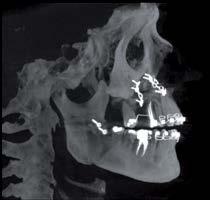

Nell’ambito della radiologia 3D ortopedica, il centro diagnostico utilizza il nuovissimo macchinario NewTom 5G XL, in grado di individuare con la massima precisione la presenza di fratture o lussazioni delle articolazioni, controllare la corretta guarigione di una frattura, valutare una lesione o una ferita causata da infezione, artrite o crescita anormale dell’osso.

Il tutto mediante una semplice e veloce scansione, grazie alla quale si otterranno diverse immagini in 3D ad altissima risoluzione e, per ottenere immagini ancora più nitide mediante un bassissimo dosaggio di radiazioni, gli esperti si avvalgono dell’innovazione racchiusa nella tecnologia Cone Beam.

Se con la radiologia tradizionale era necessario eseguire scansioni multiple, la novità introdotta dal macchinario NewTom 5G XL risiede nella capacità di fornire immagini ad alta risoluzione in un’unica scansione, mostrando nitidamente i dettagli delle articolazioni degli arti superiori e inferiori. Inoltre, a differenza della tecnologia 2D, la radiologia 3D ortopedica permette di individuare immediatamente alcune patologie come quella del metatarso, la quale richiede un allineamento visivo dedicato o una diagnosi delle micro fratture ossee.